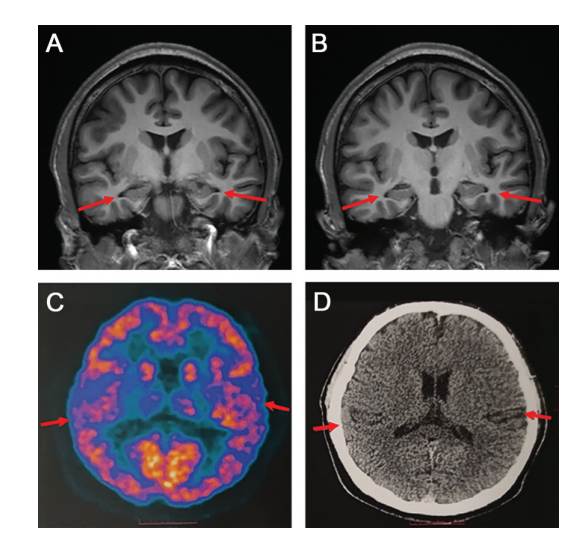

论文的作者之一、宣武医院神经内科主任医师贾龙飞告诉记者,该病例的情况非常罕见,以至于他一度不敢相信检查的结果,但医院采取了多种检测方式,包括世界权威的阿尔兹海默症检查手段——脑脊液指标检查以及PET扫描,最终医生们临床诊断该患者为阿尔兹海默症。